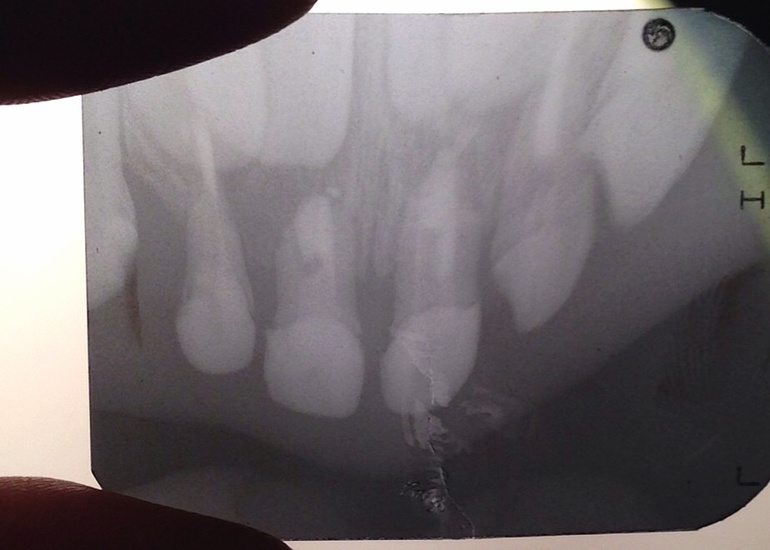

Из Курска рентген

Напомню, что ребенок сильно ударился передними зубами, единицами. Шатаются сильно ( до этого уже шатались немного)

Рентген на окне и лампе, не знаю, как лучше